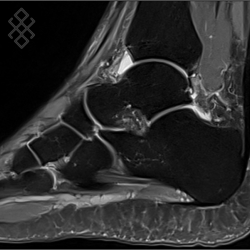

IRM de la Cheville

Vous entrez dans l'aimant, ouvert des 2 côtés, les pieds en premier et allongé sur le dos avec les bras le long du corps. Pour recueillir le signal et construire les images, vous aurez la cheville dans une antenne. Étant donné que cet examen est bruyant, vous aurez à votre disposition des tampons auriculaires pour atténuer le bruit de la machine.